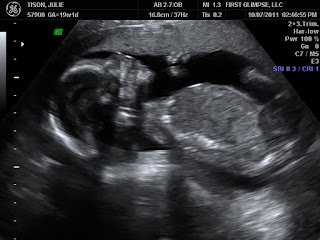

On to the exciting stuff! I had an ultrasound on Oct. 7. And we found out that my instincts were dead on again - we're having a BOY! I am so excited, but I honestly can't imagine that my excitement would have been any different had I found out it was a girl. I think I'm just happy that I get to know a little more about this sweet little baby who is squirming around in my stomach.

At the ultrasound, the baby kept moving his arm up and down, so we would see it move in and out of the picture. It was so amazing! Everything checked out fine with my appointment as well. The midwife actually told me to take half a Tylenol PM if I can't sleep ... the problem is that I never remember to actually pick up the pills when I am at the store ... I only remember in the wee hours of night. Oh well! I will actually write in on my next shopping list ... if I remember!